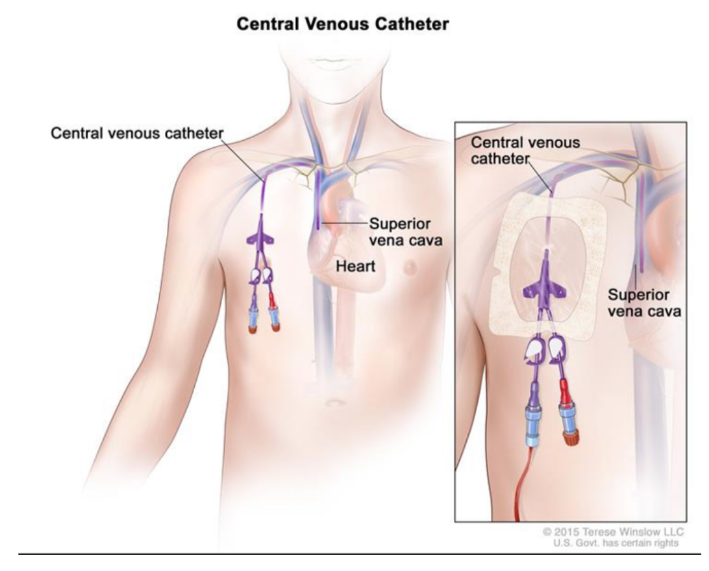

Clinical drop — venous access for lines/venous catheter

Large systematic veins are used to establish central venous access for administering large amounts of fluid, drugs, and blood

Most of these lines (small-bore tubes) are introduced through venous puncture into the axillary, subclavian, or internal jugular veins

The lines are then passed through the main veins of the superior mediastinum, with the tips of the lines usually residing in the distal portion of the superior vena cava or in the right atrium